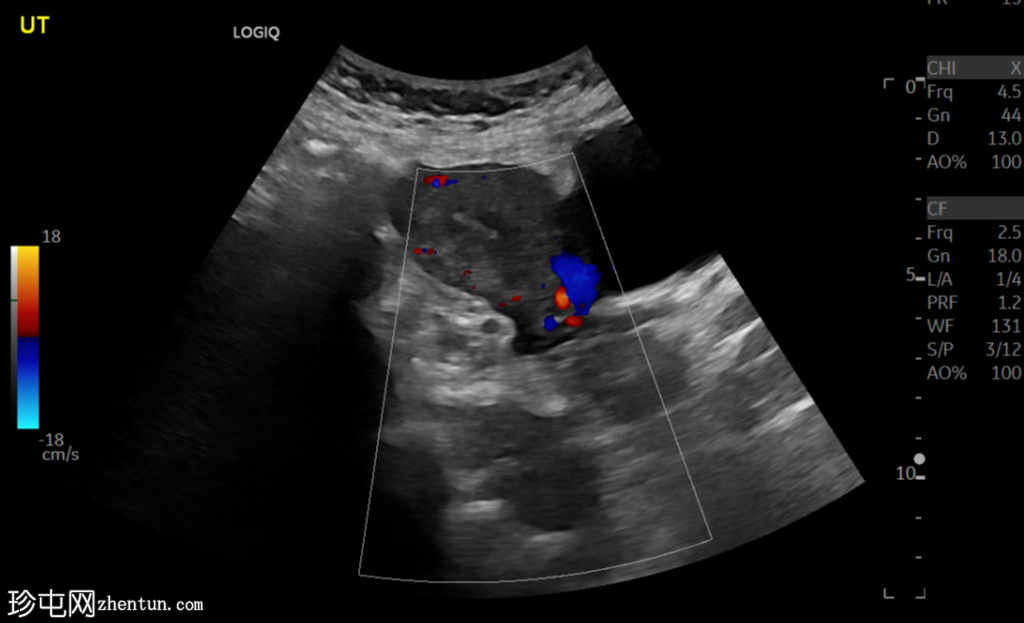

超声检查

斜切面

左侧卵巢明显增大,可见一囊肿,大小约3.2 x 2.3 cm,呈火环征,可能为黄体囊肿。左侧卵巢与子宫之间可见一管状结构,直径约1.3 cm,内含浑浊液体,未见血管,最可能为输卵管积血。以上特征提示可能为左侧异位妊娠。

未见宫内妊娠囊。